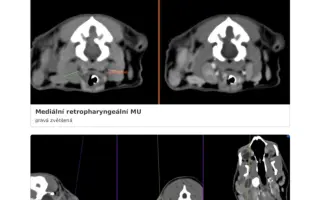

Laruška má úspešne po CT vyšetrení a operácii oboch zvukovodov !

Milí ľudia, medzičasom, v procese schvaľovania na Doniu, moja milovaná Larunka už absolvovala CT a následne do týždňa aj operáciu na klinike Vet point – AniCura u skvelého MVDr. Valáška. Už sme viac nemohli čakať. Larunke sa musel odstrániť celý pravý zvukovod aj abces, ktorý z necho vyrastal a tvoril sa stále horšie donekonečna a naviac sa odstránil aj polyp v ľavom zvukovode, o ktorom sme predtým nevedeli, ale na CT sa ukazovalo niečo, čo bolo potrebné u operácie skontrolovať a bol to nakoniec polyp. Peniažky, ktoré som musela vyplatiť na CT a operáciu musím splatiť najneskor do 1 - 2 mesiacov. CT ma stálo 450,- operácia 900,- Eur a samozrejme liečba, kontroly atď nie sú u konca. Prikladám medzi fotky aj účty, bohužiaľ takto sekane, po viac stranách, neviem to sem inak nahrať v celku, aby to bolo čitateľné. Vopred ďakujem každému za podporu čiastkou, akou môžete a chcete nám pomôcť aj za každé zdieľanie či dobrú energiu poslanú naším smerom:). S láskou najšťastnejšia mačacia mamina Evi, že to máme konečne za sebou a Larunka, najstatočnejší pacient. Ešte je pred nami cesta, ale verím, že už to bude stále lepšie, a dúfam, že aj finančne sa mi podarí to prežiť s vašou pomocou. Ďakujem zo srdca aj Doniu za možnosť a pomoc so zbierkou.

Odvtedy ju trápia vážne chronické problémy s pravým uškom – opakované zápaly, polypy, abscesy a opuchy lymfatických uzlín. Podstúpila viacero vyšetrení a zákrokov, brala antibiotiká, kortikoidy, homeopatiká aj alternatívnu liečbu. Pomohlo to len dočasne.

Momentálne je situácia kritická – uško je nepriechodné, zápaly sa vracajú a hrozí, že infekcia sa rozšíri ďalej. Veterinári odporúčajú CT alebo MRI vyšetrenie a pravdepodobne operáciu zvukovodu (abláciu).